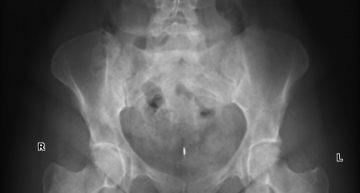

в последние три года периодически возникали боли в коленных суставах. амбулаторное и санаторное лечение приносило некоторое облегчение, на два три месяца. летом на даче стараюсь не перегружать суставы, занимаюсь посильным физическим трудом. но с августа 2013 появились сильные боли в левом тазобедренном и коленном суставах. по снимку, сделанному в поликлинике, врачи поставили диагноз: коксоартроз и возрастные изменения в коленном суставе. по предписанию врачей проколола мукосат 20 уколов и диклоберл 15 уколов, но улучшения не наступило. сейчас мучают дикие боли в левом тазоюедренном и коленном суставах, и при ходьбе очень болит берцовая кость. предложеные физиопроцедуры пройти не могу, так как практически не выхожу из дома. на некоторое время помогает нимесулид 100мг в таблетках. с каждым днем боли все сильнее, а лекарственное воздействие все меньше.